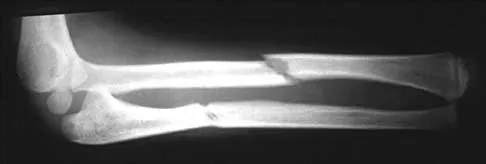

Question 99

A 65-year-old man has a painful right hip mass that has been growing for several years. A radiograph, CT scan, and photomicrograph are shown in Figures 56a through 56c. What is the most appropriate treatment?